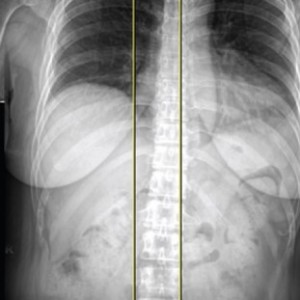

척추

척추측만증 또는 한쪽으로 기울어진 척추로 인해 체중이 한쪽 무릎에 집중된다면 장기적으로 기울어진 쪽 무릎에 관절염이 빠르게 진행됨

▲ 무릎 수술환자의 스캐노그램 엑스레이 검사